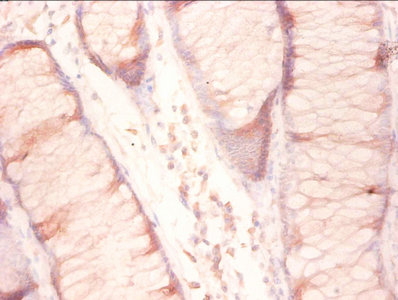

Immunohistochemistry of paraffin-embedded human colon cancer using CSB-PA02345A0Rb at diluton of 1:50